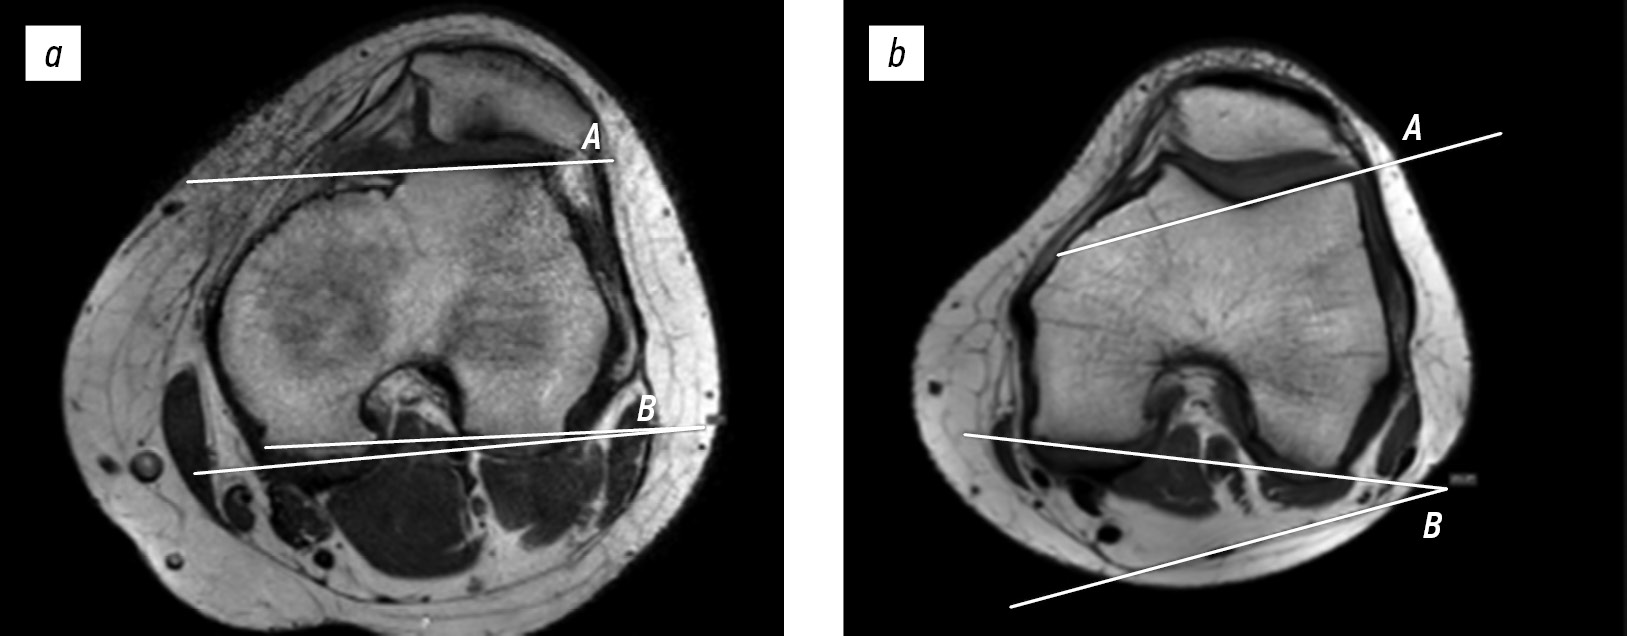

Lateral trochlear inclination was assessed using the first axial image on which the articular cartilage was visible. The inclination angle between the lateral condylar line and posterior femoral condylar line was measured. A line tangent to the subchondral bone of the posterior surfaces of the femoral condyles was intersected with a line tangent to the subchondral bone of the lateral surface of the trochlear groove. An inclination angle of <11° indicated trochlear dysplasia (Fig. 1) [12].

Fig. 1. Lateral trochlear inclination on magnetic resonance imaging in a 15-year-old female patient with patellar instability (1.2°) (a) and in a 17-year-old female patient with anterior cruciate ligament injury (21°) (b). A, line tangent to the lateral facet; B, line tangent to the posterior condylar line.